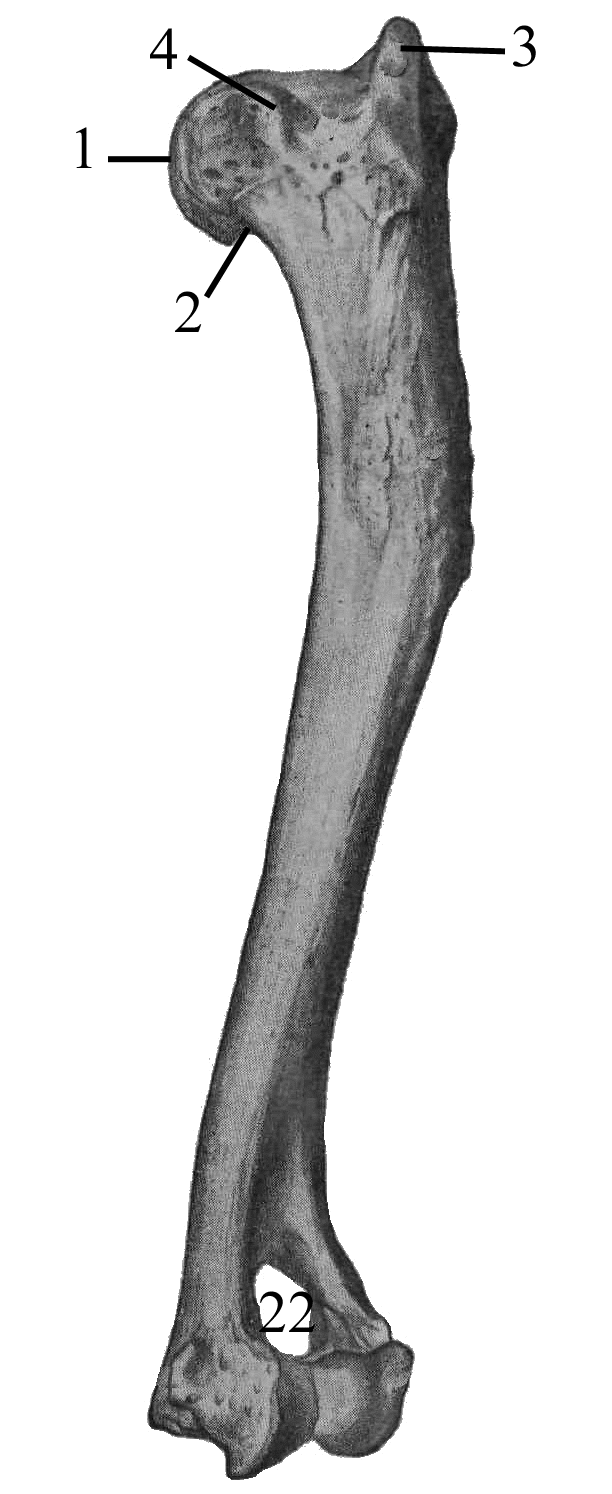

Радиоульнарный угол: строение и особенности лучевой кости